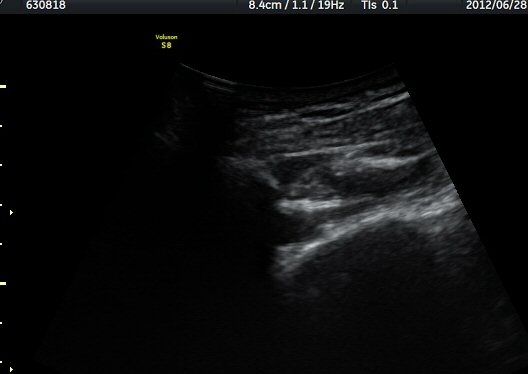

ÃÊÀ½ÆÄ °Ë»ç

¾î±ú °üÀý µÚÂÊ ÈĹæ°üÀý¼ø Ⱦ´Ü¸é°Ë»ç¿¡¼­ °üÀý¼ø ³»Ãø, °¡½Ãµ¹±â°üÀý¼ø°í¶û(spinoglenoid

notch)¿¡¼­ Àú¿¡ÄÚ ³¶Á¾ÀÌ °üÂûµÈ´Ù(±×¸² 1). ŽÃËÀÚ¸¦ À§-¾Æ·¡ ¹æÇâÀ¸·Î º¯°æÇÏ¿© °üÂûÇÒ ¶§µµ

¿ª½Ã °ß°©°ñ °¡½Ãµ¹±â(spine) ¾Æ·¡¿¡¼­ Àú¿¡ÄÚ ³¶Á¾ÀÌ °üÂûµÈ´Ù(±×¸² 2). º¼·ÏŽÃËÀÚ·Î ¹Ù²Ù¾î °ü

ÂûÇÏ´Ï  °¡½Ãµ¹±â°üÀý¼ø°í¶û¿¡¼­ Àú¿¡ÄÚ ³¶Á¾ÀÌ ´õ¿í ¶Ñ·ÈÈ÷ °üÂûµÈ´Ù(±×¸² 3, 4).